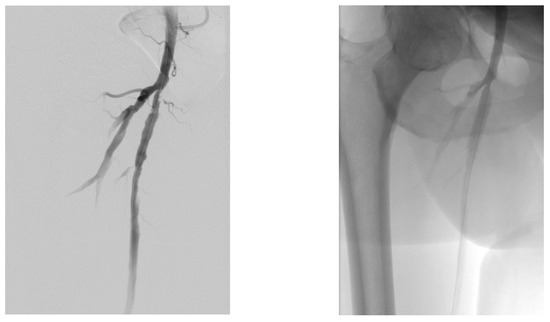

4.1. Case 1—Direct Revascularization-Minor Amputation

4.2. Case 2—Indirect Revascularization-Major Amputation